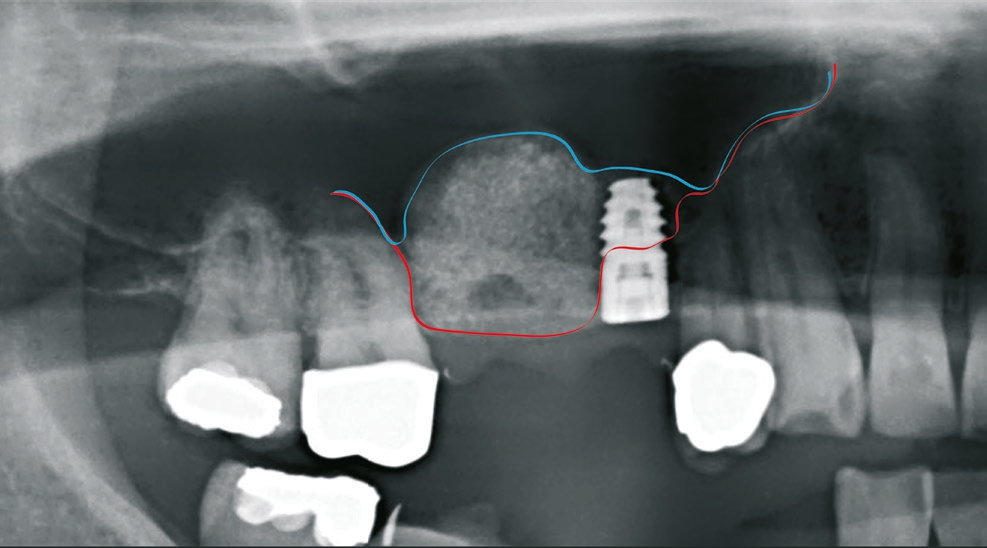

Patient 1: männlich, 50 Jahre alt, Anamnese: unauffällig; Diagnose: Schaltlücke. Knochenersatzmaterial: Geistlich Bio- Oss® (Geistlich Biomaterials) (Abb. 5 bis 10).

Dr. van Orten